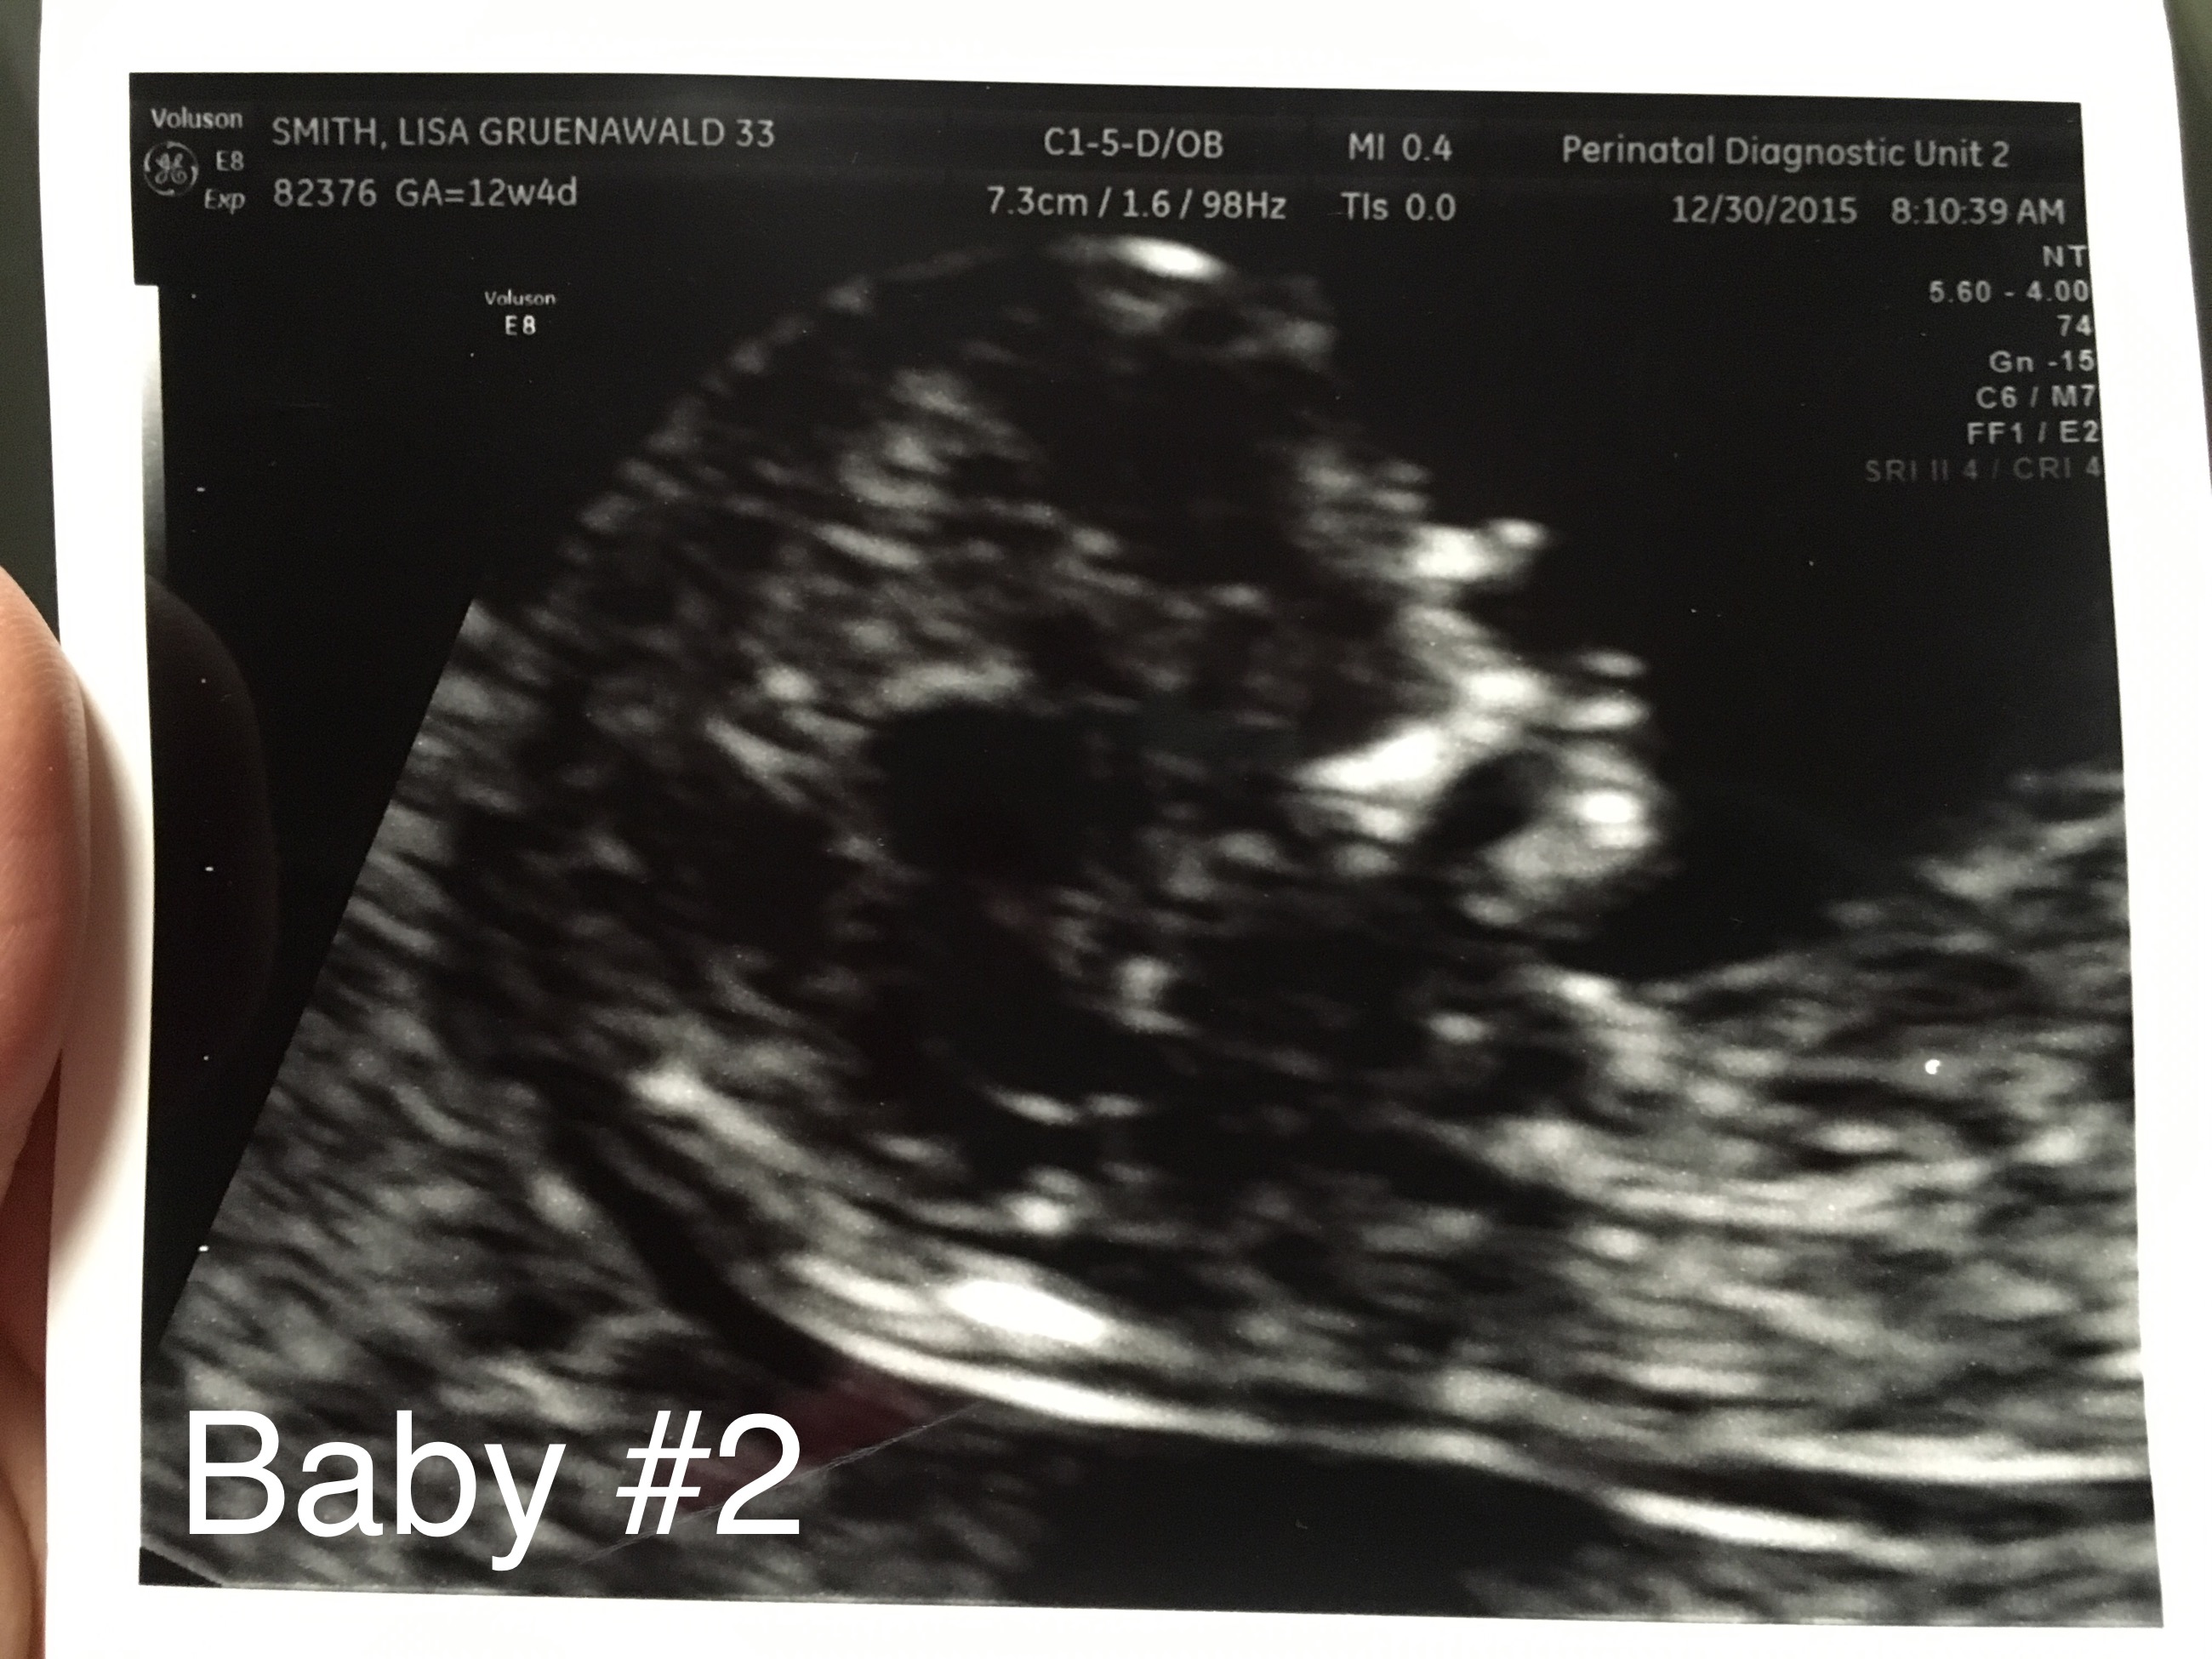

Below are my 12+4 week scan shots, I'm hoping for some gender guesses. Is the nub even visible? I've looked at tons of pics online and can't seem to make out the nub in my pic. I'm kind of thinking boy, this bub looks so much like my DS around the same time (in regards to skull shape, although this baby has a flatter face). I've attached pics of DS as well.

Here is current baby:

Attachment 29170